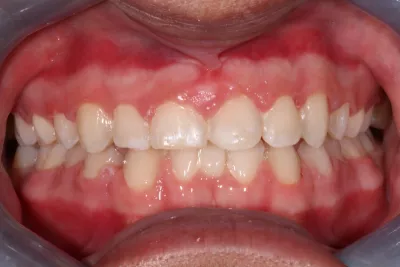

Invisalign & Teeth Whitening

6 months Invisalign & Teeth Whitening